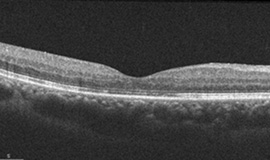

빛간섭단단층촬영(OCT)

당뇨황반부종에 대한 유리체내 주사 전

당뇨황반부종에 대한 유리체내 주사 후